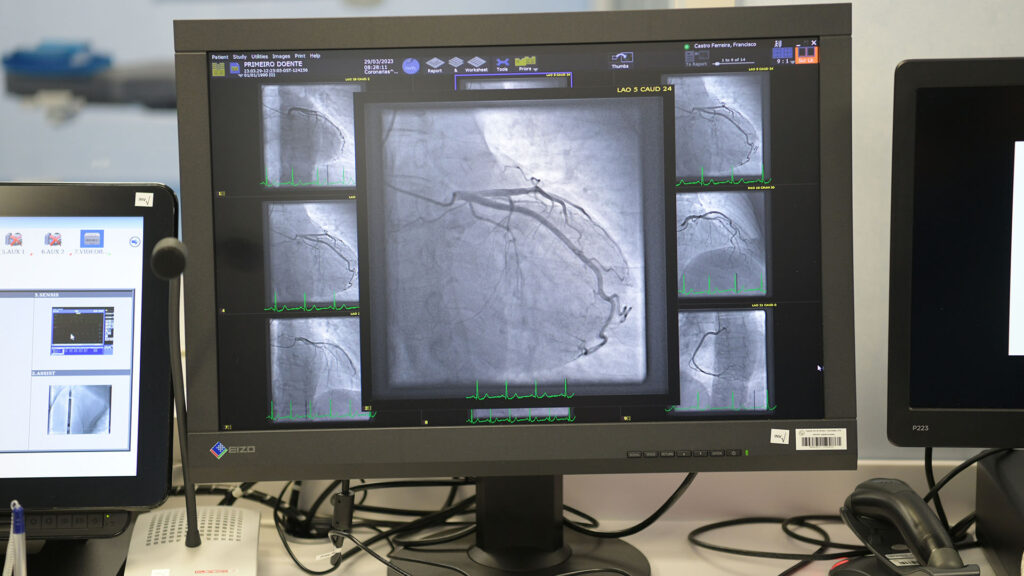

Segundo o hospital, este tipo de exames é “fundamental na avaliação de doentes com patologia cardíaca”. É utilizado, principalmente, no estudo invasivo da anatomia coronária, para identificação das lesões obstrutivas que são responsáveis, por exemplo, pelos sintomas de dor torácica na angina de peito ou no enfarte do miocárdio. Quando indicado, é possível proceder à intervenção nestas lesões, através de uma angioplastia.

Henrique Capelas informou que “hoje já foram intervencionadas as primeiras duas doentes” e irão “três vezes por semana, segundas, quartas e sextas, fazer os cateterismos ou angiografias, tudo o que for necessário nesta matéria”. Continuarão a ter a colaboração dos “médicos séniores” do hospital de Braga.